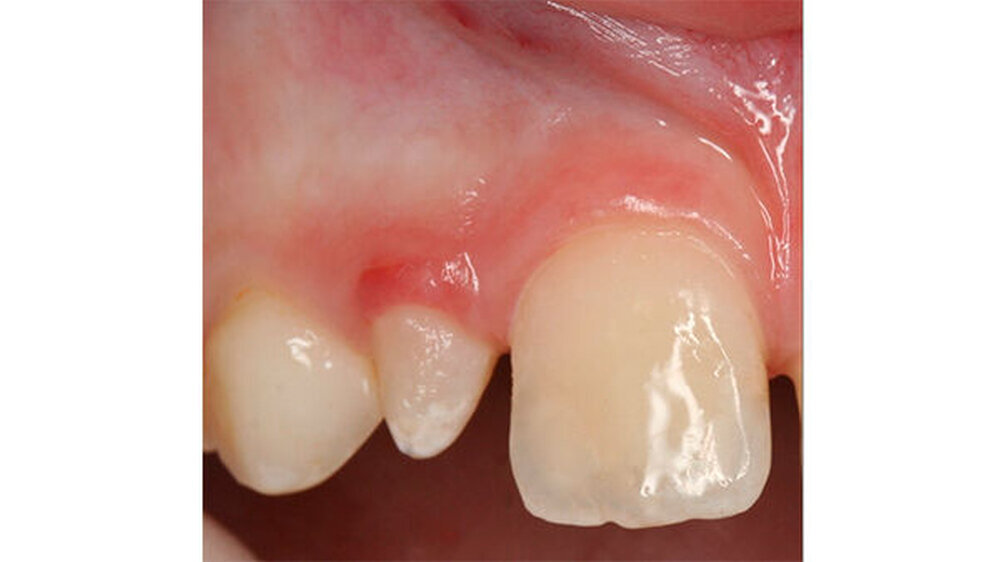

Das klinische Bild der MIH reicht von einem bis zu vier betroffenen Molaren, nur selten sind alle Zähne in ähnlicher Ausprägung geschädigt [Weerheijm et al., 2001]. Die bleibenden Frontzähne können ebenfalls betroffen sein, diese weisen allerdings in der Regel keinen Schmelzeinbruch auf und sind selten bis gar nicht überempfindlich [Weerheijm et al., 2001] (Abbildung 2).

Bisher wurde nicht beschrieben, dass die Frontzähne nur allein betroffen sein könnten. Meist wird - wenn die Frontzähne zusätzlich zu den Molaren betroffen sind - über mangelnde Ästhetik geklagt und die Kinder aufgrund ihres Aussehens gehänselt.

In schwerwiegenden Fällen kann der Einsatz eines Komposits das beste Ergebnis erzielen (Abbildungen 2, 13 und 14)